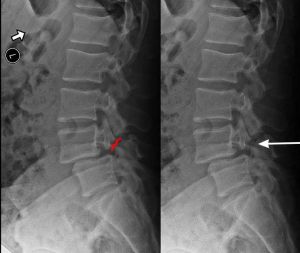

When we look at the spine from the side, we can imagine a scotty dog. It is outlined above. The pars fracture is seen as a collar around the dog's neck. Instability and movement can cause the neck to widen. We will see this below in an X-ray example.

Spondylolisthesis is most commonly found in the lumbar spine as these levels bear the most weight. To assess instability, we take x-rays of a patient bending forward (flexion) and bending backwards (extension). Normally there would be no motion. The more motion seen between flexion and extension x-rays across an injured level, the greater the patient’s symptoms usually appear.

X-RAY SHOWING A PARS FRACTURE DEFECT

THE WHITE OUTLINE SHOWS THE SLIPPAGE.